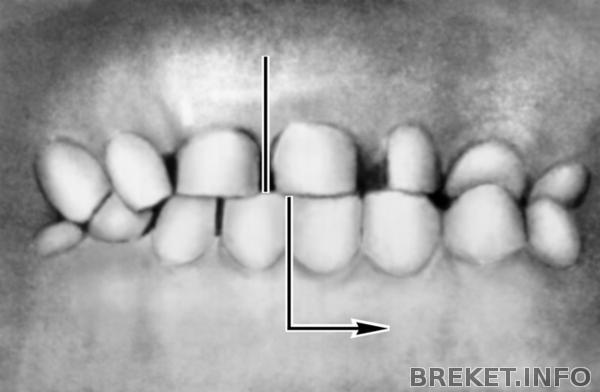

Вот картинки по перекрестному прикусу. У меня тоже если присмотреться подбородок нессиметричен и ноздря одна как будто бы больше )) вот как у этой девушке на фото - очень похоже.

В том то и дело что уздечки эти у меня строго на месте и на нижней челюсти строго между единичками и на нижней строго между единичками. Но центр не сходится, так как челюсть нижняя влево уходит при смыкании. На фото этой девушке сделали операцию. Просто не все проблемы брекетами можно решить. Визуально зубы могут быть в правильном прикусе с посощью брекетов, а сам сустав (нижняя челюсть) также не правильно смыкаться и это грозит куче проблем со здоровьем. Или после брекетов профиль может измемиться и ассиметрия восстановиться?? Хорошо бы если так... Просто когда смещение нижней челюсти поначиталась и проблемы с дыханием и глотанием могут быть и воспаление нервов зубов и проблемы с деснами... ((( Просто меня удивляет почему тот орт смотрел и долго пытался понять как у меня смыкается челюсть и предупредил что нужна операция бы, а второй просто не смотрел как я смыкаю зубы, а наклеил брекеты и делов. Не хочу обижаться на своего орта...но почему моя орт ничего про это не сказала??? не заметила? не захотела замечать?? а ведь правда присмотреться - у меня не симметричный подбородок... (((((( Неужели брекетами можно симметрию и овал лица изменить в нужном порядке??

Да, прикус перекрёстный.

Центр ВЧ у Вас на месте. А центр на нижней челюсти смещён на ползуба. Центр тягами исправляется,не переживайте